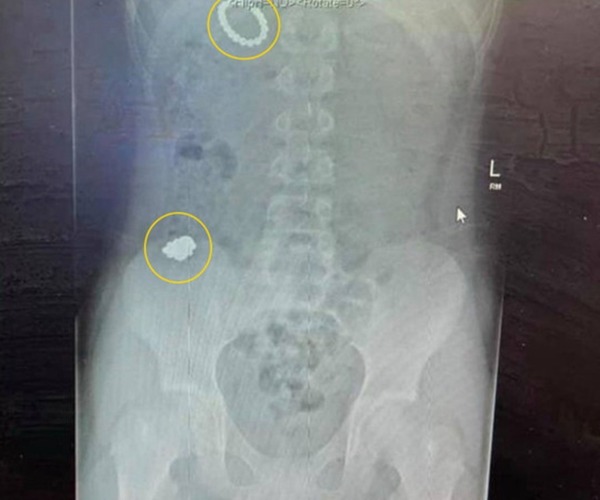

母親得知後隨即將 Morrison 帶到醫院,不過 X 光檢查後顯示, Morrison 足足吞下了 54 粒小磁珠,並有可能會燒傷其器官更有可能喪命,於是急需進行手術。之後他整整 10 天無法動彈,同時腸道不時流出的綠色嘔吐液,讓他只能通過輸液管餵食,最終於兩周後出院。醫生表示,他吞下 54 顆後仍能安然無恙,實在「相當幸運」。